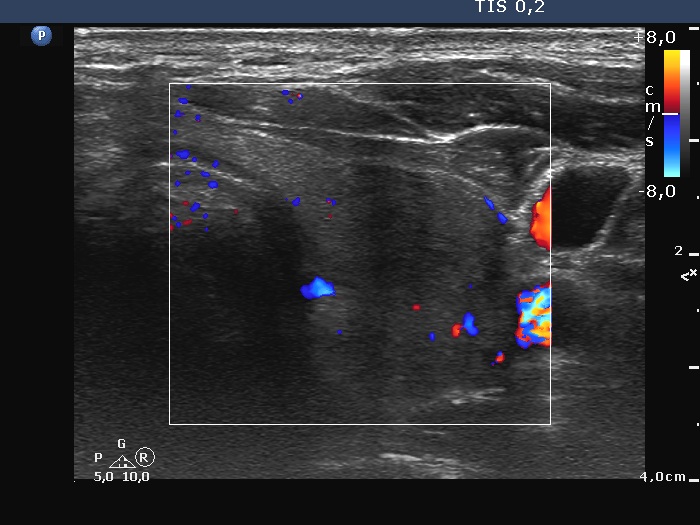

Left lobe, transverse scan, color Doppler mode. The hypoechoic part of the lobe is avascular.